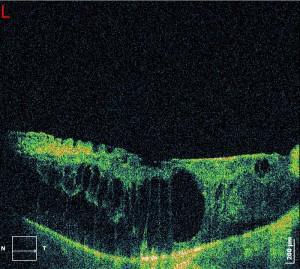

Diabetic Macular Oedema can be diagnosed by fundoscopy (examination of fundus under dilated pupils), as well as by fundus photograph, where we can depict the macula and the optic nerve. A very useful tool is called Optical Coherence Tomography (OCT), where the operator (optometrist or ophthalmologist) can measure the thickness of the oedema and can detect also the presence of cysts between the retinal layers, any serous retinal detachment, the presence of epiretinal membrane and if there is blood between the retinal layers. With this technology, we can also compare the thickness of the oedema when the patient gets some treatment for the oedema.

OCT with Diabetic Macular Oedema (DMO)